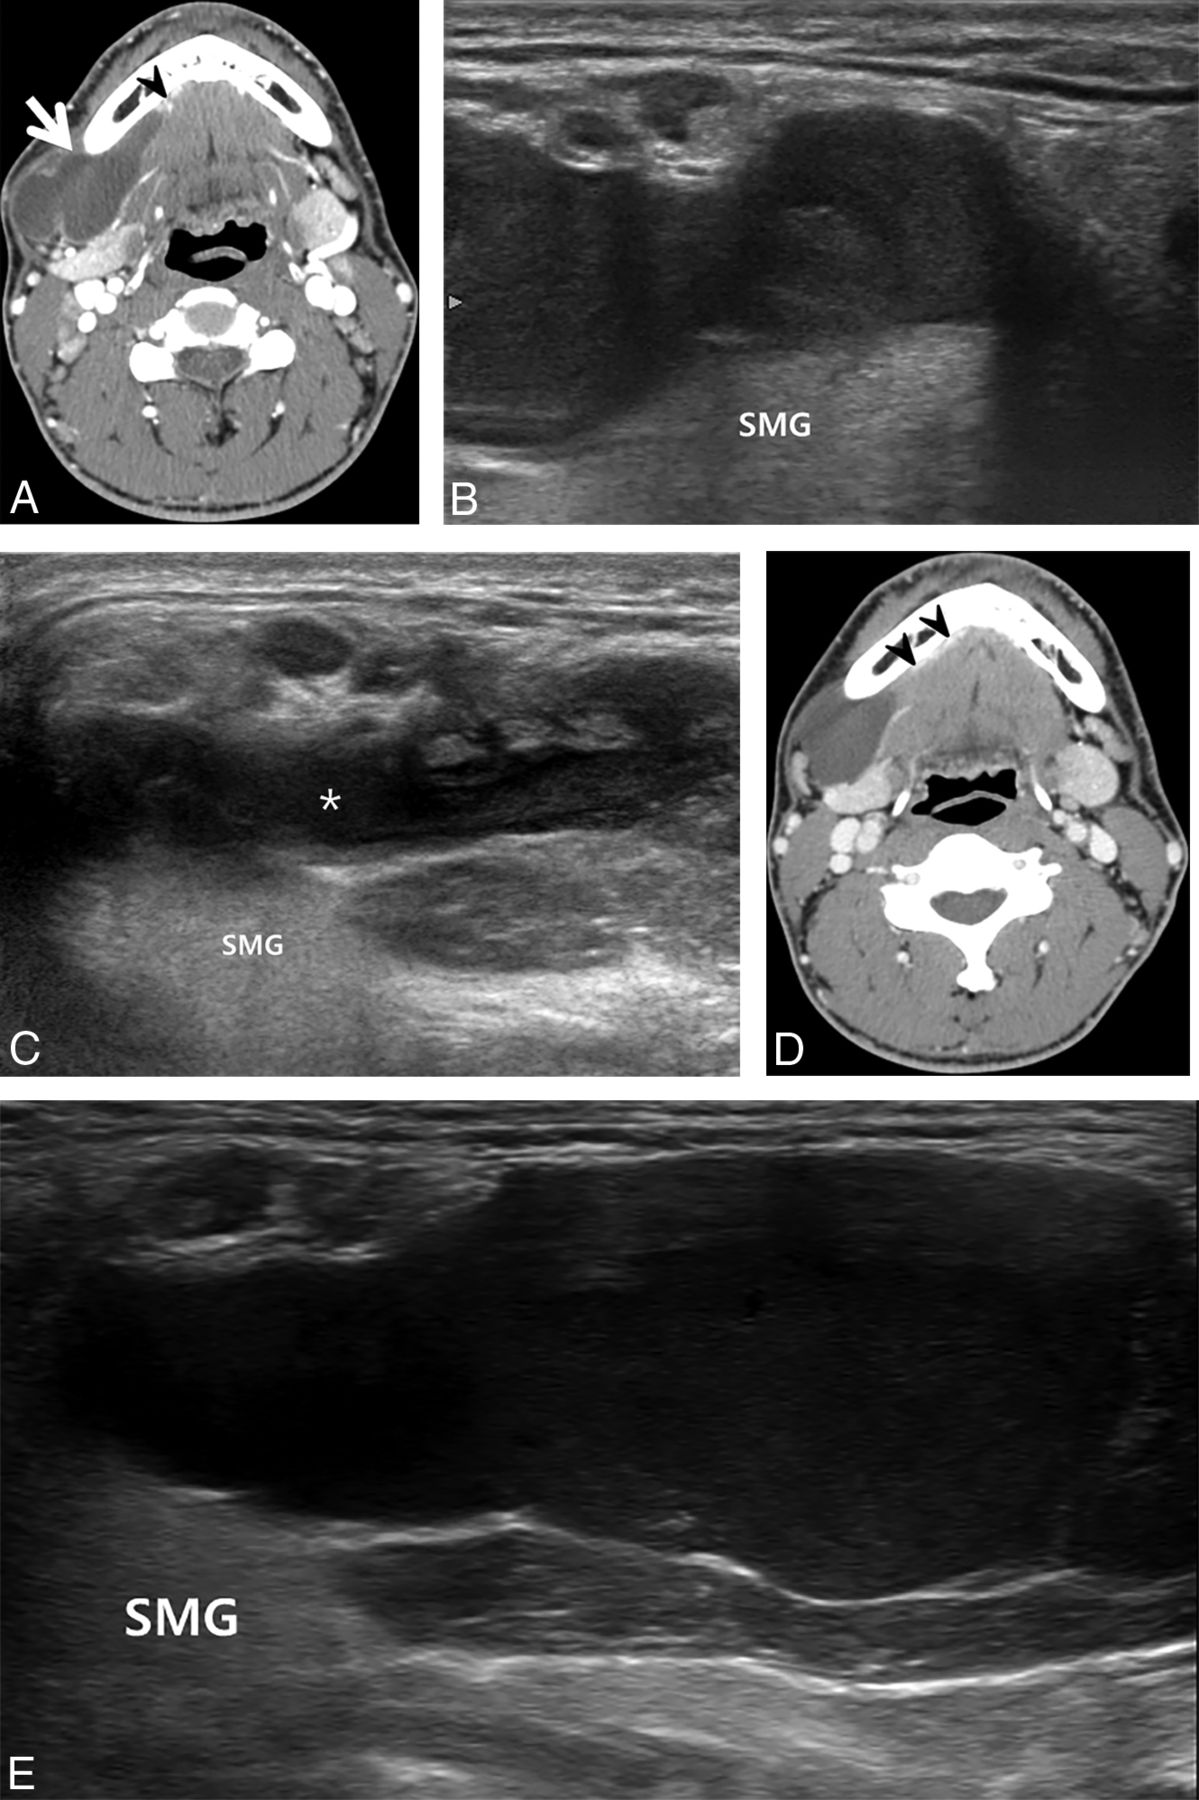

A 32-year-old man with a plunging ranula in the right submandibular space for the past 16 months. A, Pretreatment contrast-enhanced axial CT image shows a well-defined lobulated cystic mass (arrow) in the right submandibular space showing direct contact with the herniated right sublingual gland (arrowhead). B, Pretreatment oblique sonogram shows a fluid collection in the right submandibular space. C, Sonogram 1 month after ethanol ablation demonstrates the remaining fluid in the same space (asterisk). D, Contrast-enhanced axial CT image 34 months after ethanol ablation shows the cystic mass in the right submandibular space, adjacent to the herniated right sublingual gland (arrowheads). E, Oblique sonogram 34 months after ethanol ablation also demonstrates a cystic mass in the same space, showing an increase in size compared with C. SMG indicates submandibular gland.